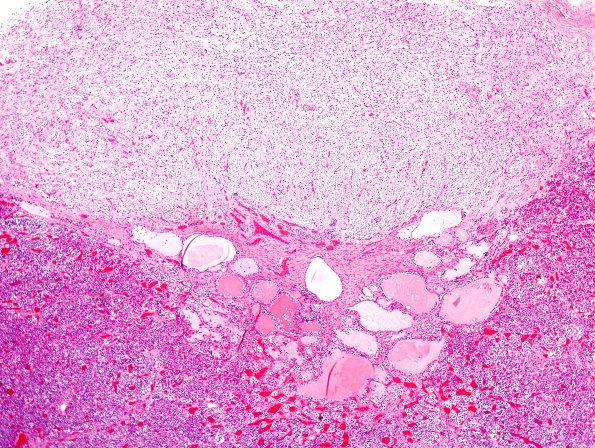

7B1-3 Numerous intermediate lobe cysts seen at different magnifications. (H&E)